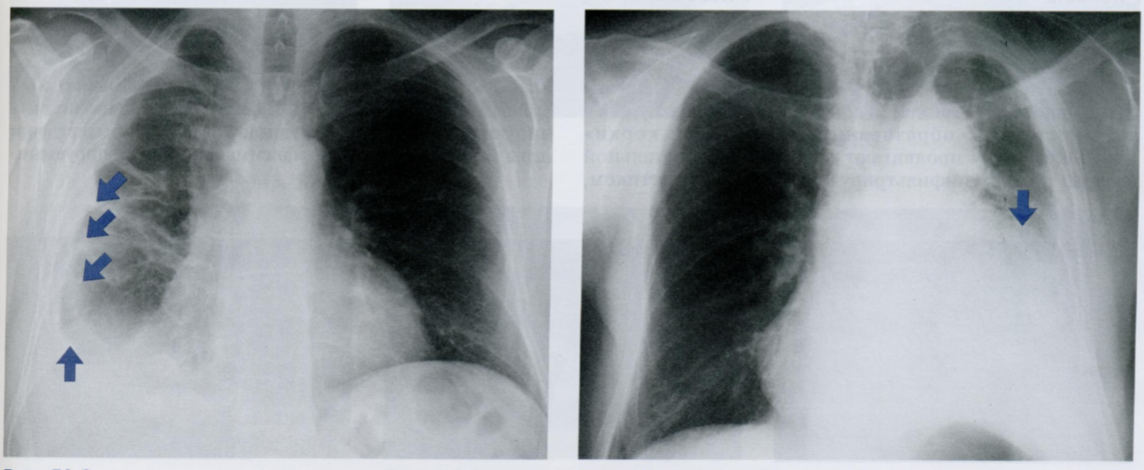

Q

Оцените снимки.

Обратите внимание на диафрагму и верхушку пораженного легко. Как называется эта опухоль?

Рентгеновская томография и КТ дают более детализированную информацию об опухолях плевры.

На Rx снимке показан пациент с опухолью Панкоста (21) в верхушке правого легкого.

Причина высокого стояния купола диафрагмы (стрелка) на стороне поражения заключается в параличе правого диафрагмального нерва, вызванном прорастанием опухоли.

При КТ четко видна инфильтрация мягких тканей грудной стенки (косая стрелка). Также определяются неоднородная структура опухоли (21) и смещение средостения влево (горизонтальная стрелка).

Однако сканирование в легочном окне (нижнее КТ) показываст, что узурации верхних ребер (22) пока еще отсутствуют.